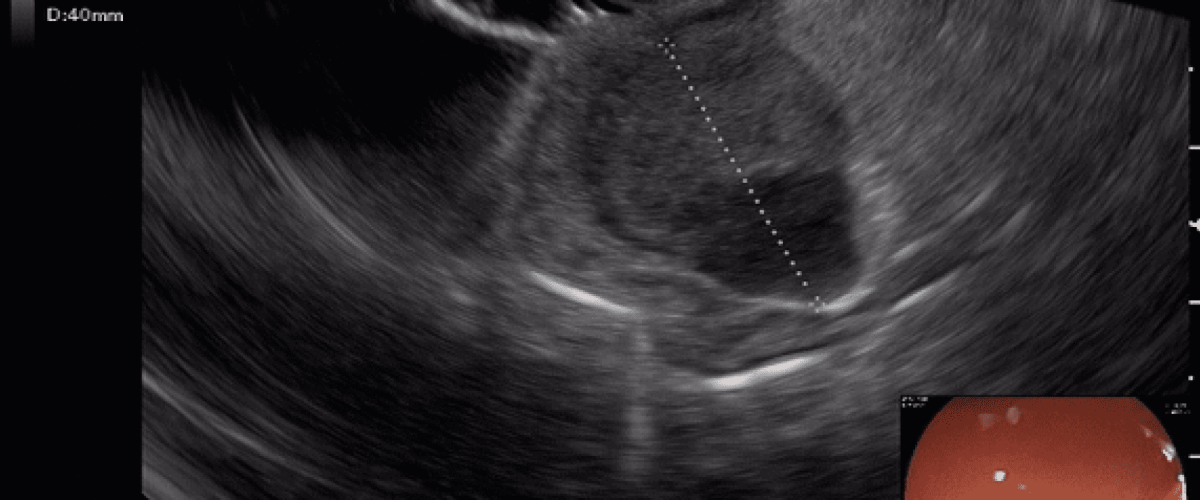

A ecoendoscopia, também conhecida como ultrassom endoscópico, é o método de escolha para o estudo e o diagnóstico dessas lesões, principalmente quando estas atingem 1 cm ou mais de tamanho. Lesões menores, dependendo da localização e história clinica, podem ser acompanhadas pela endoscopia tradicional.

O exame de ecoendoscopia é capaz de definir a sua origem, tamanho e possíveis características preocupantes. Quando indicadas, a punção ou a biópsia por agulha podem ser realizadas durante o exame, determinando o diagnóstico definitivo com excelente acurácia.